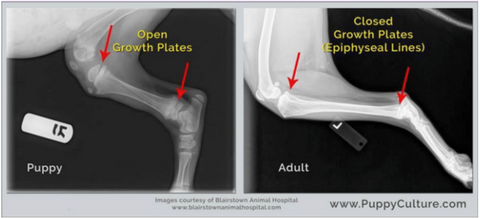

At the end of long bones we can find bone surrounded by layers of soft developing cartilage – this is know as growth plates or epiphyseal plates. This area contains rapidly dividing cells that allow bones to become longer until they reach puberty but they are also the weakest areas of the growing skeleton and very vulnerable to injury! Once a growth plate is closed it becomes a stable and inactive part of the bone.